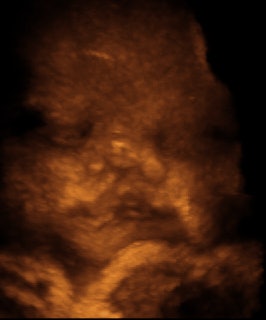

![]() |

| Motion artifact simulating cleft lip in 32-week fetus. Image courtesy of Dr. Dolores Pretorius. |